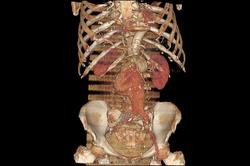

Наблюдение Tatarin

Женщина 77 лет. Жалобы на боли в животе. Пальпируется образование в околопупочной области живота. Аневризмы брюшной аорты и обеих общих подвздошных артерий.